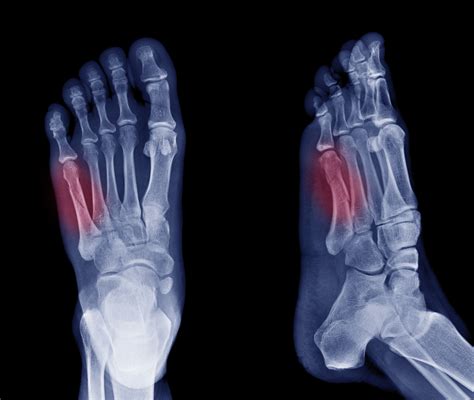

Jones Fracture of the Foot: Symptoms, Treatment, and Recovery

While home remedies are often sufficient for mild cases, persistent or worsening pain necessitates a visit to a specialist. A podiatrist can perform physical exams and utilize imaging, such as X-rays, to see if the bone on outside of foot is the result of a skeletal alignment issue or a soft tissue condition.